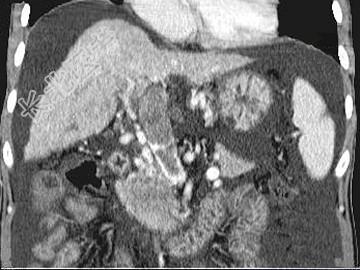

- 单项选择题女,50岁, 曾患乙型肝炎,肝硬化多年, 右上腹胀痛1月余,CT检查如图所示, 最可能的诊断为 ( )

A、肝硬化、腹水伴胆管细胞癌

B、肝硬化、腹水伴原发性肝癌

C、肝硬化、腹水、肝癌并门脉癌栓

D、肝硬化、腹水并肝脓肿

E、肝硬化、腹水并肝血管瘤